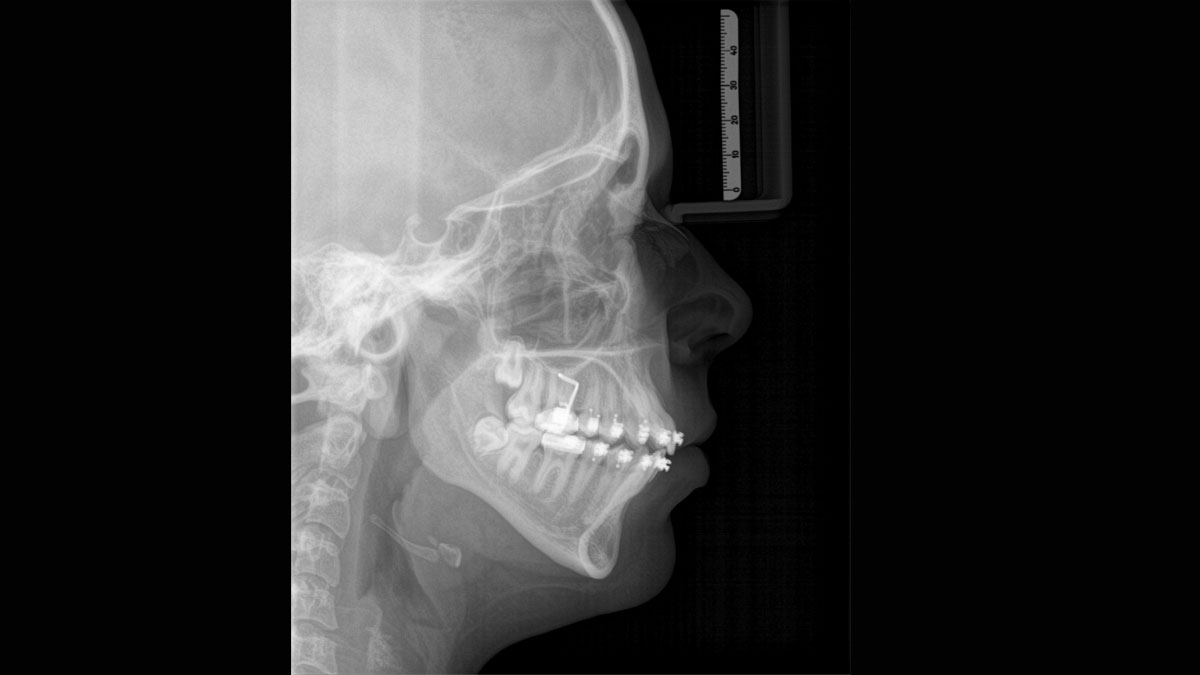

Het hoogwaardige 2D/3D-röntgenapparaat met uitgebreide mogelijkheden voor elke praktijk. Of het nu gaat om een puur 2D-apparaat of een 3D-module, de Orthophos S is een betrouwbare partner die helemaal is geoptimaliseerd voor dagelijkse taken. De CsI Plus-sensor met autofocusfunctie geeft heldere beelden, zelfs in anatomisch moeilijke gevallen. De automatische patiëntpositionering in combinatie met het gepatenteerde occlusale bijtblok maakt een eenvoudige en tijdbesparende patiëntpositionering mogelijk. Voor gebruik in orthodontie is de Orthophos S ook verkrijgbaar met een optionele ceph-arm. Uw praktijk toekomstbestendig houden is voor ons belangrijk en daarom kan de cephalometrische arm op elk moment achteraf worden ingebouwd.

De ceph-arm kan op elk moment aan de rechter- of linkerkant van het apparaat worden toegevoegd. Het kan worden besteld op het moment van aankoop of achteraf worden gemonteerd.

Met gemotoriseerde schedel- en voorhoofdondersteuning, automatische meting van de schedelbreedte, laser lichtlijnen en geïntegreerde handvatten voor extra stabiliteit.